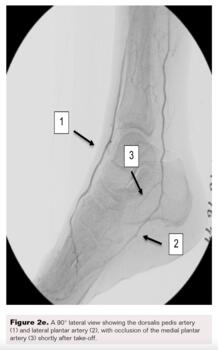

A right lower-extremity angiogram was performed using ultrasound guidance for antegrade access of the proximal superficial femoral artery (Figure 2A). Fluoroscopic acquisition demonstrated no significant disease in the superficial femoral artery (Figure 2B) and popliteal artery (Figure 2C), with no significant stenosis seen in the anterior tibial artery, PTA, and peroneal artery (Figure 2D). Pedal angiography demonstrated a complete pedal-plantar loop formed by the DPA and the lateral plantar artery (LPA) (Figure 2F).

However, the entirety of the medial plantar artery (MPA) distribution was chronically occluded shortly after take-off (Figure 2E and Figure 2F). Super-selective angiography revealed chronic total occlusion of the medial branch of the first common plantar digital artery arising from the first plantar metatarsal artery (Figure 2G). Angiography also revealed an occluded accessory branch arising medially from the superficial branch of the MPA.

The anatomy of the arteries supplying the hallux is complex, with variants being common. In this patient, an atypical accessory branch arising from the superficial branch of the MPA was present. While the arterial anatomy of hallux-supplying arteries and its corresponding variants are not readily discussed in recent literature, certain textbooks do depict an accessory branch arising from the superficial branch of the MPA.2 The accessory branch of this patient, in particular, communicated with the first dorsal metatarsal artery arising from the DPA (Figure 2F) and the superficial branch of the MPA communicated with the medial branch of the first common plantar digital artery arising from the LPA (Figure 4C). In general, using the angiosome concept, the blood supply to the hallux consists of 3 main avenues: (1) the first dorsal metatarsal branch arising from the DPA; (2) the plantar digital arteries arising from the first plantar metatarsal artery, which is a branch of the LPA; and (3) the superficial branch of the MPA.3,4 The latter 2 sources of blood supply were absent in this case.